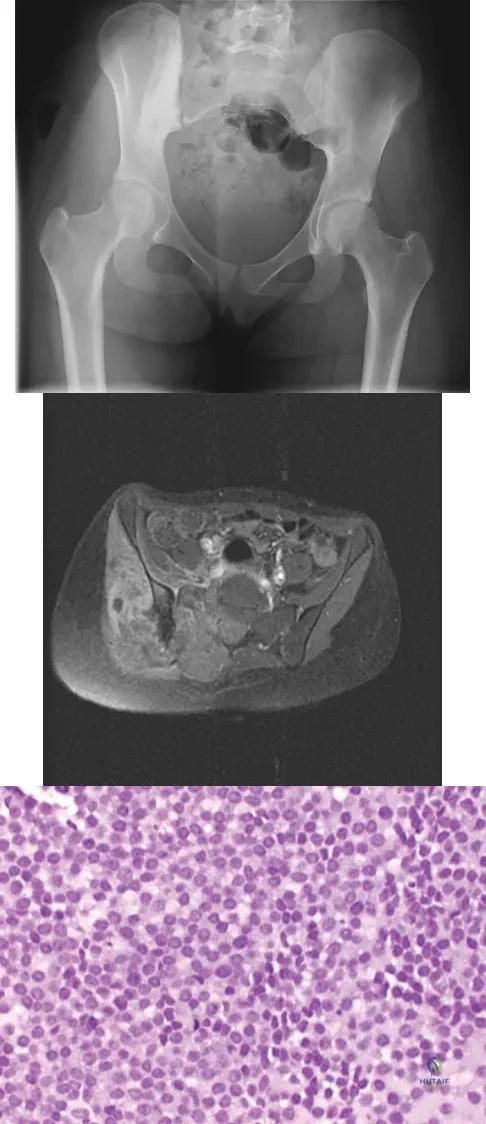

A 16-year-old girl has had hip pain for 1 year. Approximately 2 months ago she noted the development of a hard mass in the right buttock that has steadily increased in size. She now reports severe pain in the right buttock, with radiation down the leg and numbness involving the right foot and toes. A radiograph is shown in Figure 70a and an axial postcontrast T1-weighted MRI scan is shown in Figure 70b. A biopsy specimen is shown in Figure 70c. The chest CT shows multiple lung metastases. Treatment of this lesion should consist of

A 10-month-old boy has multiple skeletal lesions and a skin rash that he has had since he was a newborn. Based on the radiographs and biopsy specimens shown in Figures 79a through 79d, what is the most likely diagnosis?